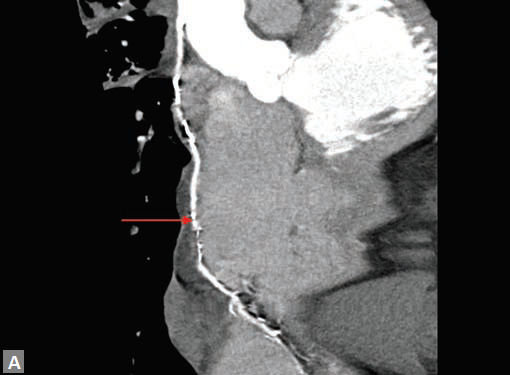

CT is the preferred tool of investigation of coronary bypass grafts (Fig. 9). Reversed saphenous vein grafts (SVGs) are optimally studied consistently. Anastomotic sites are studied effectively. However, distal anastomosis of venous graft to obtuse marginal branch (OM) is relatively difficult to evaluate because of diminishing caliber of native vessel. Arterial grafts pose a small challenge due to artifacts of associated surgical clips (Figs 10A and B). Ostium and proximal part of graft are assessed well. However, distal anastomotic site may be difficult to assess on occasions. RIMA graft, posterior descending artery (PDA) graft, gastroepiploic artery graft can also be studied. Stenosed venous grafts

can be stented and the same can be evaluated by CT (Fig. 11). Like native RCA, RCA grafts (Figs 12A and B) are more susceptible to motion artifacts when compared to LAD and OM grafts. Catheter angiogram can be used to answer specific queries after CT angiogram.